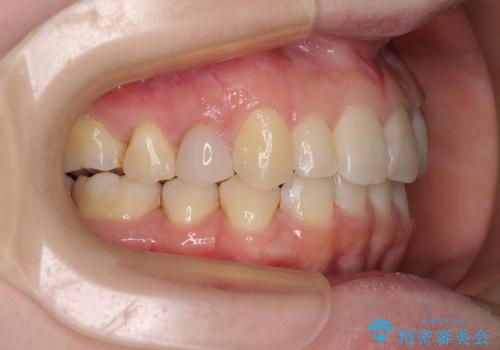

先天欠損のある歯列 インビザライン矯正

- 上顎前歯の突出感を気にして来院された患者様です。

下顎前歯2本が先天欠損しており、上顎歯列に対して、下顎歯列がアンバランスに小さい状況でした。

左右上顎側切歯2本が矮小歯であるため、上顎の抜歯ではなく、IPR(歯と歯の間を削る)と歯列全体の後方移動によってバランスを整えることとしました。

目立ちにくい装置を希望されたため、インビザラインにて治療を行うこととしました。